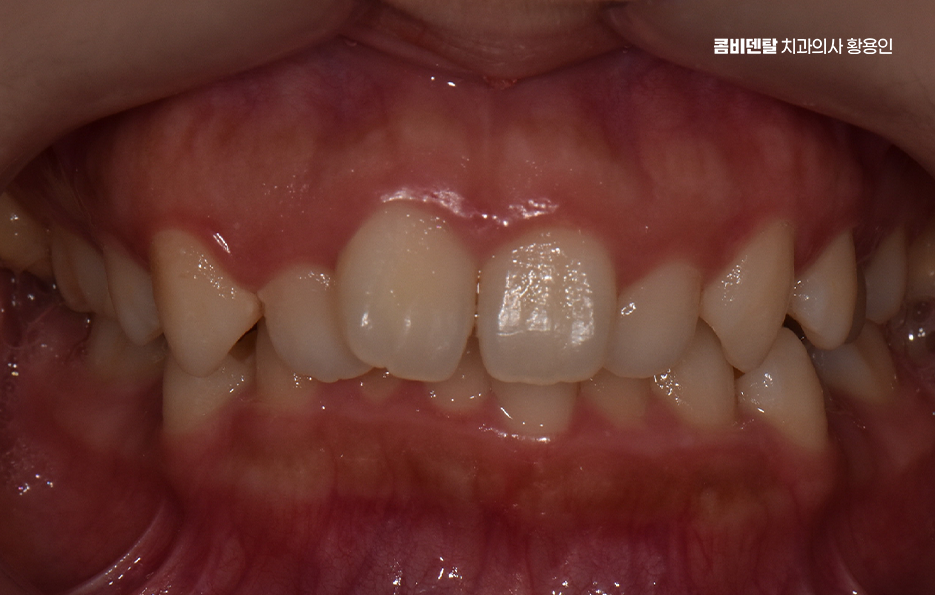

돌출입이라는 표현은 단순히 입이 튀어나와 보인다는 인상만을 의미하지는 않으며 치아가 앞으로 기울어져 있거나, 잇몸뼈 자체가 앞으로 나와 있거나, 입술 두께와 근육 사용 습관까지 복합적으로 작용해 나타나는 경우가 많아서 겉으로 보기에는 비슷한 돌출입처럼 보여도, 실제 교정 계획은 사람마다 크게 달라질 수 있었어요.

비발치 돌출입 교정 가능한 대표적인 케이스는 치아 배열의 공간이 비교적 충분한 경우로서 치아가 전체적으로 가지런하지는 않지만, 심하게 겹쳐 있지 않고 잇몸뼈 안에 어느 정도 여유 공간이 있는 경우에는 발치 없이도 치아를 뒤쪽으로 이동시키는 것이 가능한 경우가 있었어요.

특히 앞니가 약간 앞으로 기울어져 있으면서 입술 돌출이 심하지 않은 경우에는 비발치 교정으로도 인상 개선 효과를 기대할 수 있어요.

턱뼈의 위치와 형태도 중요한 기준이 되며 잇몸뼈 자체가 과도하게 앞으로 튀어나와 있는 골격성 돌출입의 경우에는 비발치 교정만으로는 한계가 있는 경우가 많은 반면 턱뼈의 위치는 비교적 정상 범위에 있고, 치아 배열로 인해 돌출이 강조되어 보이는 경우라면 비발치 교정이 현실적인 선택지가 될 수 있었어요.